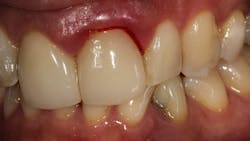

Pocket depth. Classic studies have shown that the deeper the periodontal pocket (the space between the gum and the tooth), the harder it is to remove the bacteria and calculus (tartar).2 For example, one study suggests that when probing depths are in the 1–3 mm range, removal of calculus during scaling and root planing can be 86% effective. That number drops to 32% when pockets are 6 mm or greater (figure 2).